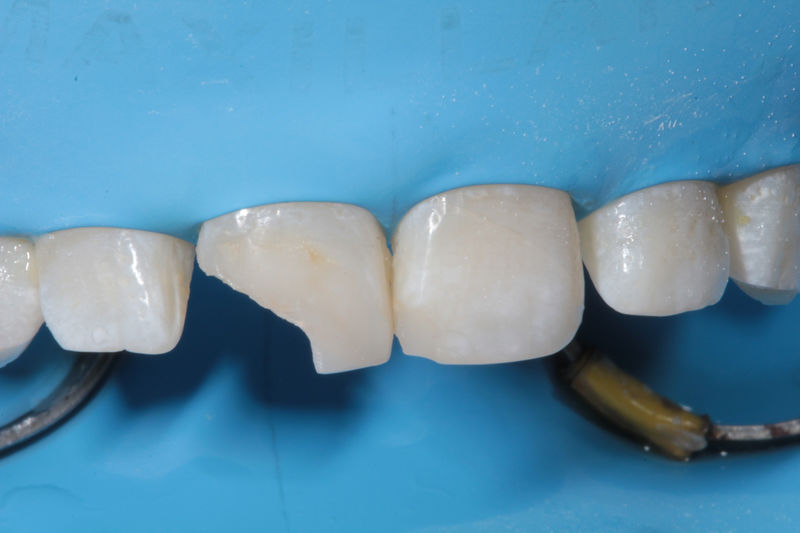

Disciplina fundamental de la Odontología enfocada en el diagnóstico, prevención y tratamiento restaurador de las piezas dentales que han sufrido daños. Su objetivo principal es devolver al diente su equilibrio biológico, funcional y estético cuando su integridad ha sido alterada. Resinas directas, incrustaciones, coronas.

Restauraciones fabricadas en el laboratorio con materiales estéticos, los cuales cubren de manera parcial dientes posteriores. Se utilizan primariamente para restaurar dientes con caries, fracturas y/o defectos amplios. Para poder enviar el caso al laboratorio se toman impresiones utilizando materiales de impresión o técnicas modernas digitales.

Restauraciones fabricadas en el laboratorio con materiales estéticos, los cuales cubren de manera total dientes anteriores y posteriores. Se utilizan primariamente para restaurar dientes con caries, fracturas y/o defectos amplios, así como soportes de puentes. Para poder enviar el caso al laboratorio se toman impresiones utilizando materiales de impresión o técnicas modernas digitales.